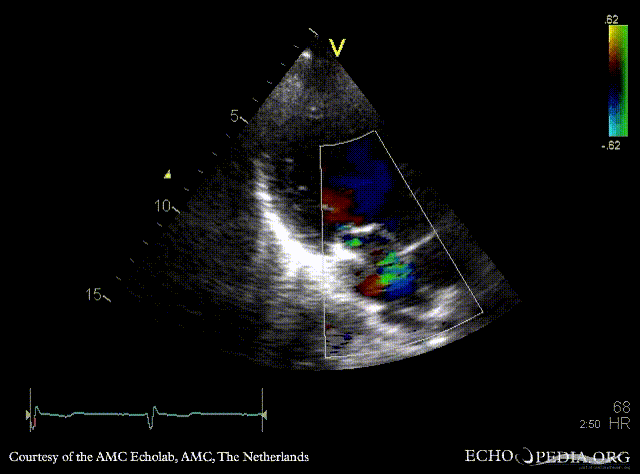

E00580.gif E00581.gif

PSAX with Color Doppler A3CH with Color Doppler